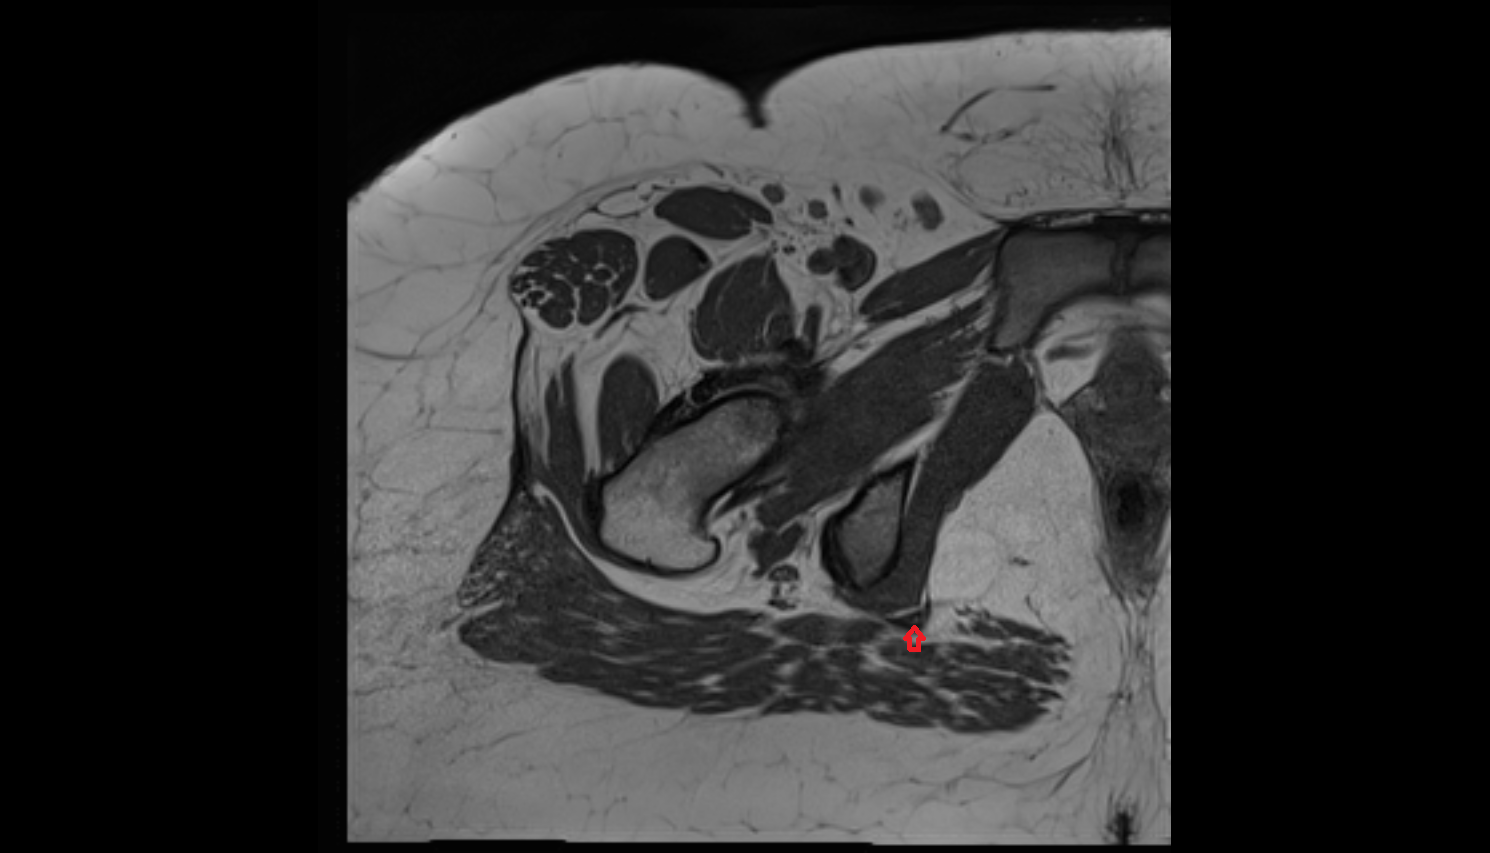

- Rectum

- Vagina

- Uterus

- Levator ani muscle